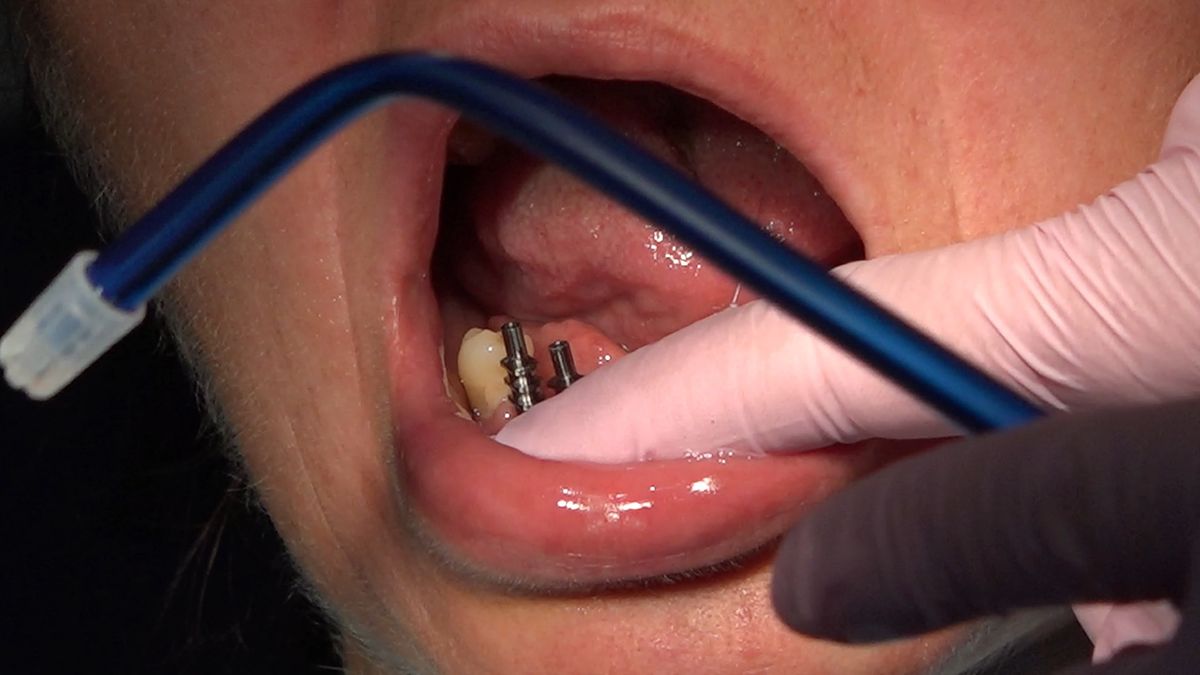

Tematem przewodnim 3 Sesji X Sezonu Practiculum Implantologii była protetyka na implantach. Lekarze przeprowadzili wiele procedur implantoprotetycznych pod kierunkiem dr n.med. Violetty Szycik, w tym oddanie prac przykręcanych i odsłonięcie implantów. Pod kierunkiem dr Małgorzaty Piotrowskiej wykonywali pobieranie wycisków z poziomu implantów tradycyjnie i za pomocą skanera. Zabiegi i ćwiczenia poprzedziły wykłady, które przeprowadził także technik dentystyczny Marek Wiligała.